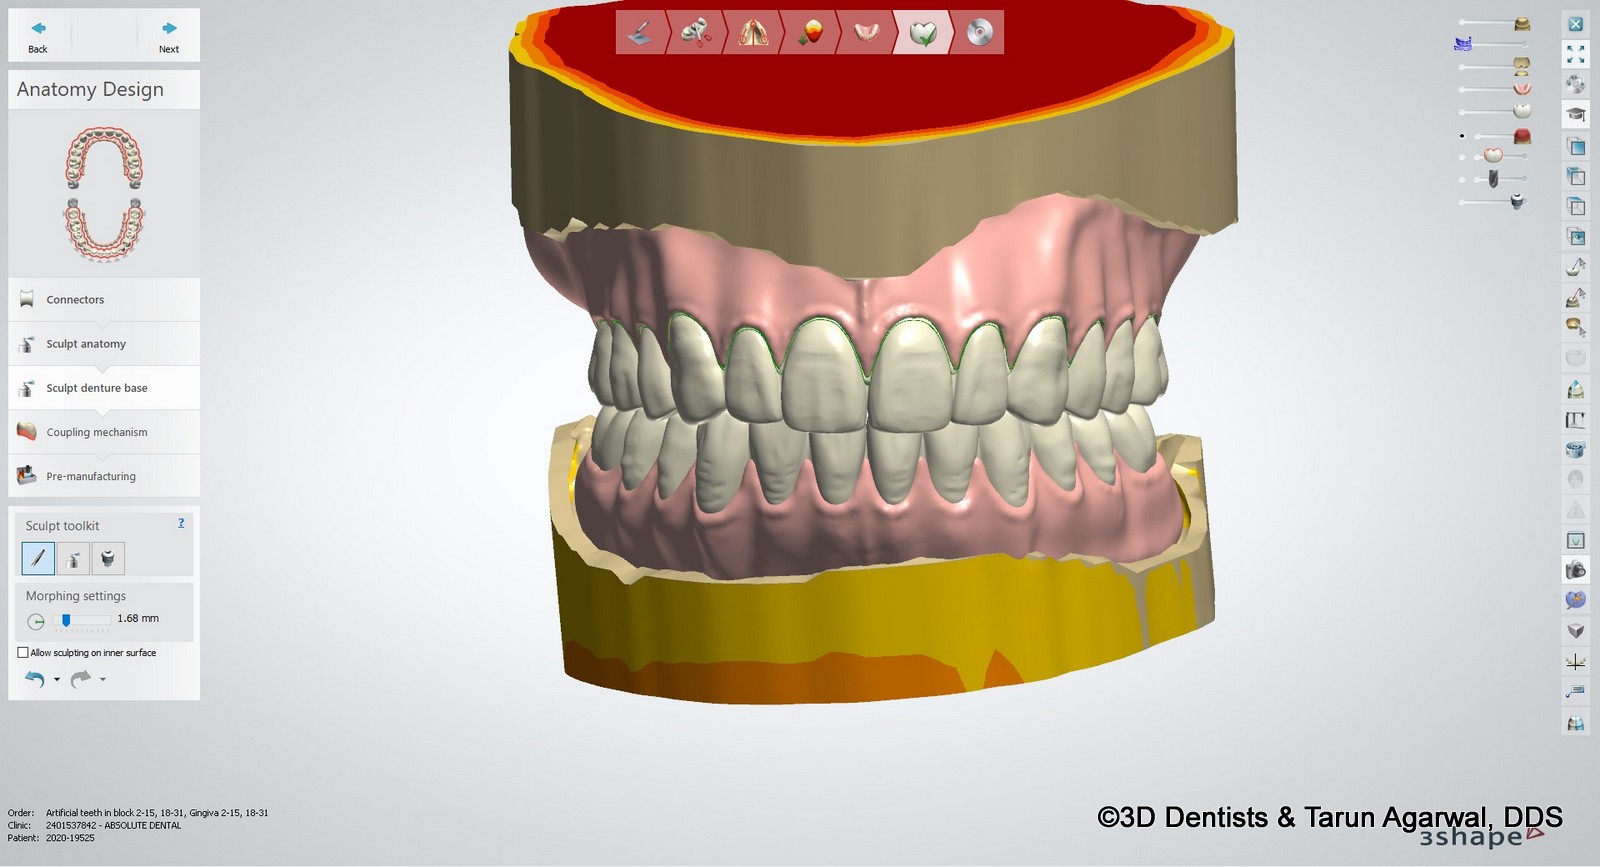

Here the lab can take this information and transfer it to the denture design software. In this case 3Shape Dental Studio was used. The overlay is used to ‘set’ the denture teeth at the new position to allow more tooth to show at rest and at smile.

The final denture design was completed in the software. The lower teeth were intruded to not create excessive overbite.